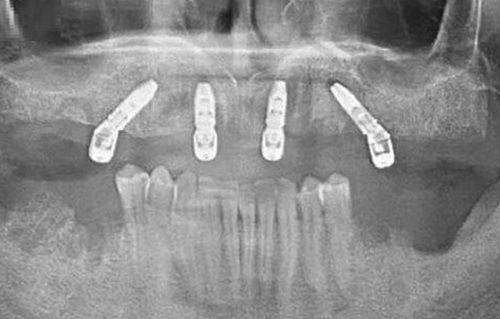

他经手的种植实例数量惊人,种植成功实例超5万例,其中疑难种植病例就有2万多例。这庞大的数字背后,是他无数个日夜的努力和对每一位患者的负责。对于半/全口疑难无牙颌种植技术,他有着自己独特的见解和方法。特别多患者牙齿缺失情况复杂,传统的种植方法可能并不适用,但在张医生这里,都能找到合适的解决方案。

在GBR上颌窦内外提升方面,他也有着一定的操作技巧。上颌窦提升对于特别多医生来说是一个挑战,但张医生凭借着自己的经验和技术,能够较好地完成这项操作,为患者的种植手术创造有利条件。

在张会敏医生擅长的众多项目中,半/全口疑难无牙颌种植技术是他比较拿手的。半/全口牙齿缺失对于患者来说是一个特别困扰的问题,不仅影响美观,还会影响正常的饮食和生活。

对于这类患者,张医生会精良行详细的口腔检查,了解患者的口腔状况和身体情况。然后根据患者的具体情况,制定个性化的种植方案。在种植过程中,他会严格按照方案进行操作,确保种植体的位置和稳定性。

他会考虑到患者的经济情况和需求,选择合适的种植体材料。而且在种植后,他也会对患者进行跟踪和指导,让患者能够更好地适应新的牙齿。特别多患者在接受张医生的半/全口疑难无牙颌种植手术后,都能重新拥有正常的咀嚼功能,生活质量得到了较大的提高。